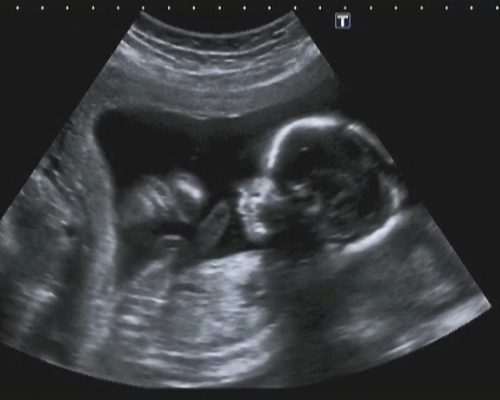

Polihidramnij (lat. Polyhydramnion) – POVEĆANA KOLIČINA PLODOVE VODE, je pojam koji označava količinu plodove vode veću od 2000 ml. Otkriva se ultrazvukom i to određivanjem indeksa plodove vode (engl. AFI-amniotic fluid indeks) koji se provodi između 36. i 42. tjedna trudnoće. Ultrazvukom se mjere okomiti džepovi plodove vode u četiri kvadranta, mjere se zbrajaju te se dobije AFI. Izrađene su tablice, količine plodove vode u odnosu na tjedne trudnoće, tako da se situacija s količinom plodne vode može precizno pratiti. Polihidramnij se dijagnosticira kada je indeks plodne vod veći od 24.

Kako se podova voda stvara, tako se i resorbira (razgradnja tvari i upijanje). Najčešći uzroci veće količine plodove vode su fetalne malformacije. Malformacija (lat.) je defekt organa ili većeg dijela tijela u embrionalnom razvoju koji nastaje prije završetka razvoja organa. Kod takvih malformacija stvaranje plodove vode je uredno, no nedostaje resorpcija plodove vode. Takvim načinom je onemogućena i sama cirkulacija plodove, te se ona nagomilava.